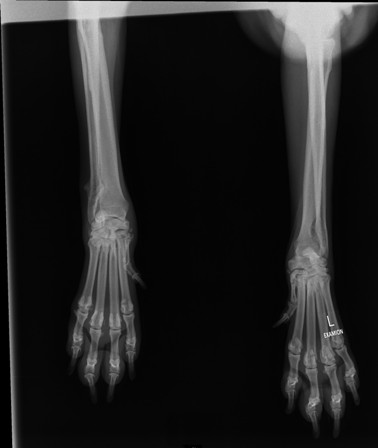

Ania hatte uns darum gebeten, mit Dario zur Klinik fahren zu dürfen, da er Probleme mit einem dicken Gelenk am Hinterlauf hatte. Am 12.01.17 war Ania mit ihm in der Tierklinik,

wo er untersucht und geröntgt worden war. Die Röntgenaufnahmen haben leider ein stark vergrößertes Herz gezeigt, sowie den Verdacht auf Knochentumor ergeben. Zur Sicherheit

wurde ein weiterer TA konsultiert, der die Diagnose leider bestätigte und zudem auch noch

einen Lungentumor diagnostizierte. Die Ärzte rieten dringend zur Euthanasie.